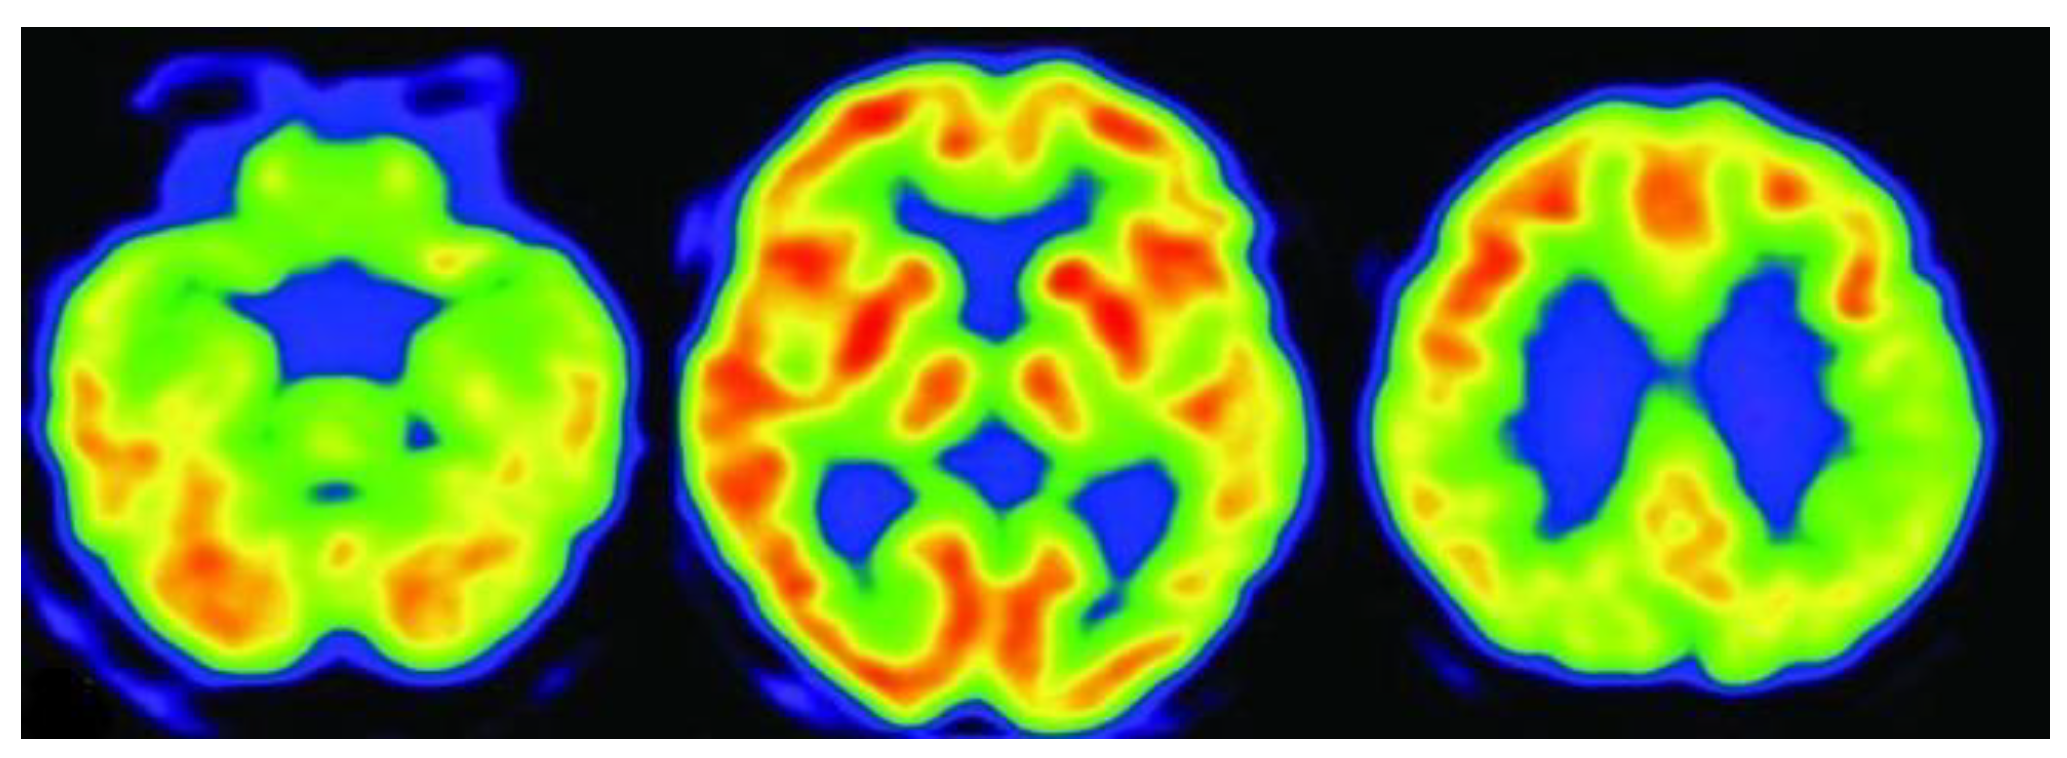

3.3. Positron Emission Tomography (PET)

3.4. Fluorodeoxyglucose Positron Emission Tomography (FDG-PET)